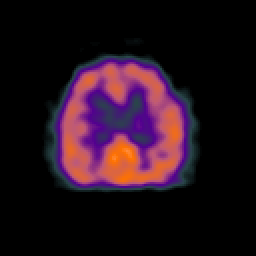

Normal aging, overlay -- Slice #37

[Home][Help][Clinical] Slice 37